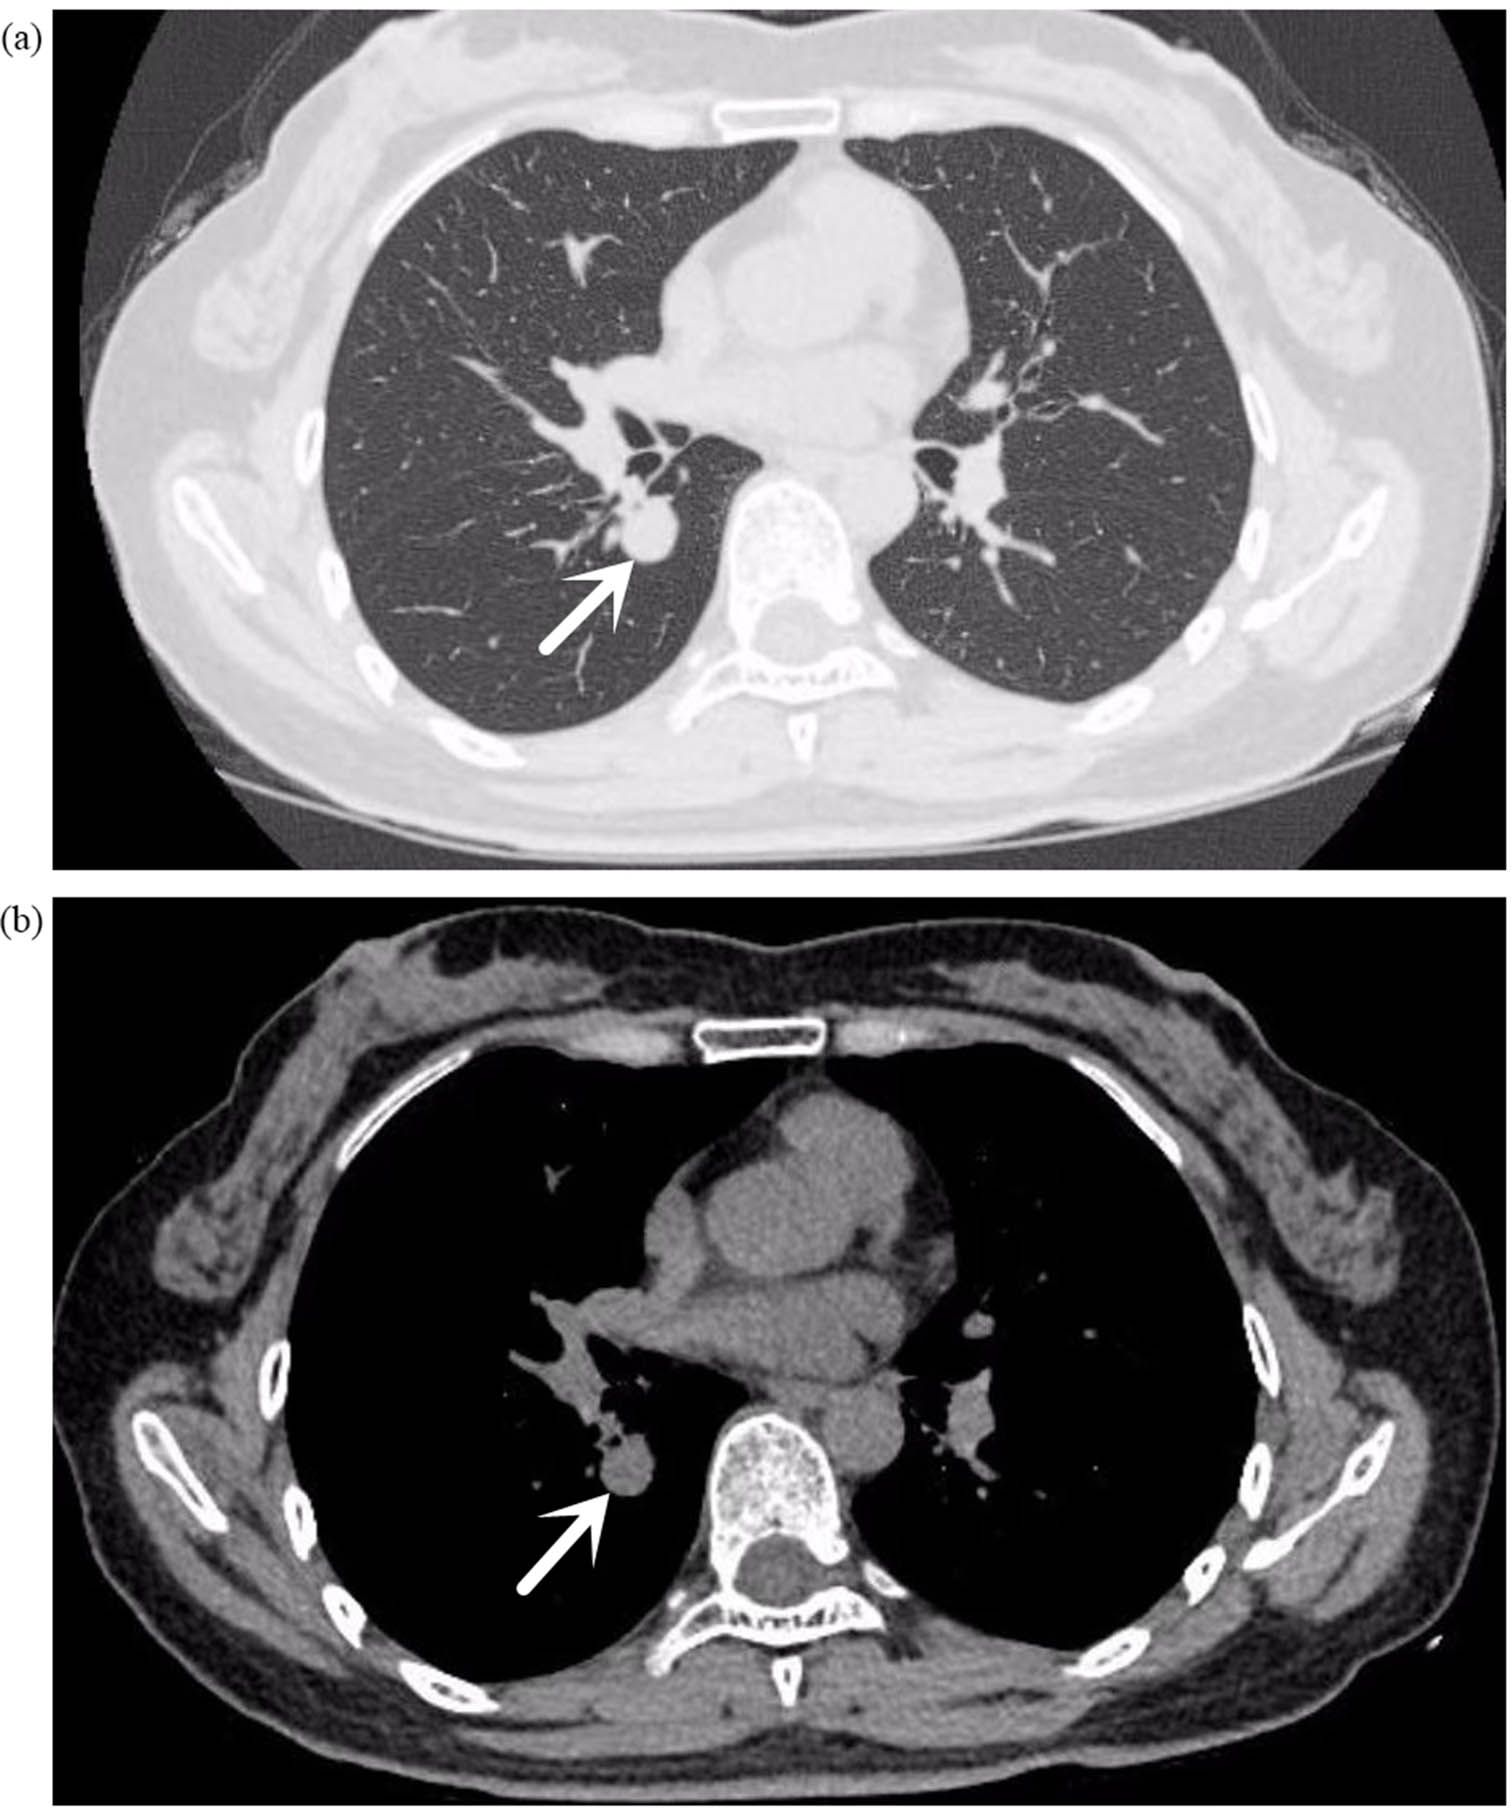

A 52-year-old female was admitted to the Second People’s Hospital of Liaocheng on 26 September 2023, presenting with a 2-month history of coughing and recurrent haemoptysis. The haemoptysis involved fresh blood that filled her mouth but was not substantial in quantity; this occurred three times. A chest computed tomography (CT) scan in July 2023 revealed bilateral pulmonary nodules. Anti-inflammatory and haemostatic medications temporarily resolved the haemoptysis, but coughing persisted. A follow-up CT revealed a small nodule in the right lower lung lobe (Figure 1), with a recommendation for a contrast-enhanced scan. Throughout her illness, her mental state, appetite, sleep, and body functions remained normal, with no weight loss. She had endoscopic polypectomies 5 years and 1 year ago. Her medical history excludes hypertension, coronary heart disease, diabetes, cerebrovascular diseases, mental illnesses, hepatitis, tuberculosis, malaria, and close contact with infectious diseases. She is up to date on vaccinations and has no history of trauma, blood transfusion or allergies to medications or foods.

(a) (Lung window), (b) (mediastinal window) chest plain CT: small nodules in the dorsal segment of the right lower lobe, with smooth margins. The arrow indicates the location of the tumor.

Upon admission, sputum smears revealed no acid-fast bacilli. Lung tumour marker screenings (CEA, CA125, CA-125, and CYFRA21-1) were unremarkable, and routine laboratory tests did not reveal any notable abnormalities. A low-dose CT scan of the chest with targeted enhancement on 26 September 2023 identified nodular shadows in the right lower lobe (Figure 2), raising suspicion of a tumour. Bronchoscopic biopsy or thoracic surgery was advised. Additionally, multiple ground-glass opacities were observed in both lungs, which may indicate hyperplastic or chronic inflammatory lesions, necessitating further monitoring. Linear opacities in both lungs and potential chronic inflammation were noted, with re-examinations scheduled. An abdominal CT on 27 September 2023 detected calcified lesions in the liver. Cardiac ultrasound revealed no notable structural or flow abnormalities. Ultrasound of superficial lymph nodes (neck, axilla, and groin) revealed no pathological changes. Venous ultrasound of the lower extremities was also normal, with no issues detected in deep or superficial veins. Brain magnetic resonance imaging (both plain and enhanced scans) revealed no significant lesions. Bronchoscopy on 28 September 2023 identified a smooth, pedunculated mass obstructing the airway in the dorsal segment of the right lower lobe, which moved slightly with respiration and was prone to bleeding upon contact. A biopsy was deferred to minimise the risk of bleeding (Figure 3). The ECT scan on 29 September 2023 revealed the following: (1) increased metabolic activity in the left first anterior rib, suggesting the need for follow-up in 3–6 months; (2) increased metabolic activity in both knee joints, consistent with degenerative changes; (3) similar changes in the cervical spine; and (4) no notable abnormalities in other skeletal regions, although further imaging may be considered as needed.

(a) (Lung window), (b) (mediastinal window) chest target-enhanced CT: small nodules in the dorsal segment of the right lower lobe, with punctate calcifications visible within it, surrounded by multiple punctate and nodular shadows; nodular growth was seen in the dorsal segment of the bronchus.